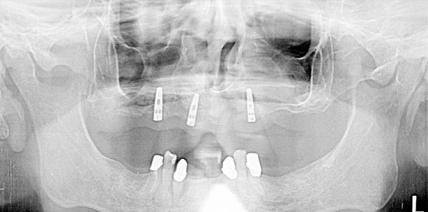

Autor verschiedener Fachartikel in mehreren dentalen Fachzeitungen über Modellherstellung; Hilfsmaterialien und Implantattechnik

• 2007 Entwicklung und Referent des Kurses: Das perfekte Implantatmodell und der individuelle Abformlöffel - Fundament für Qualität, Innovation & Sicherheit (Support durch picodent und Nobel Biocare)